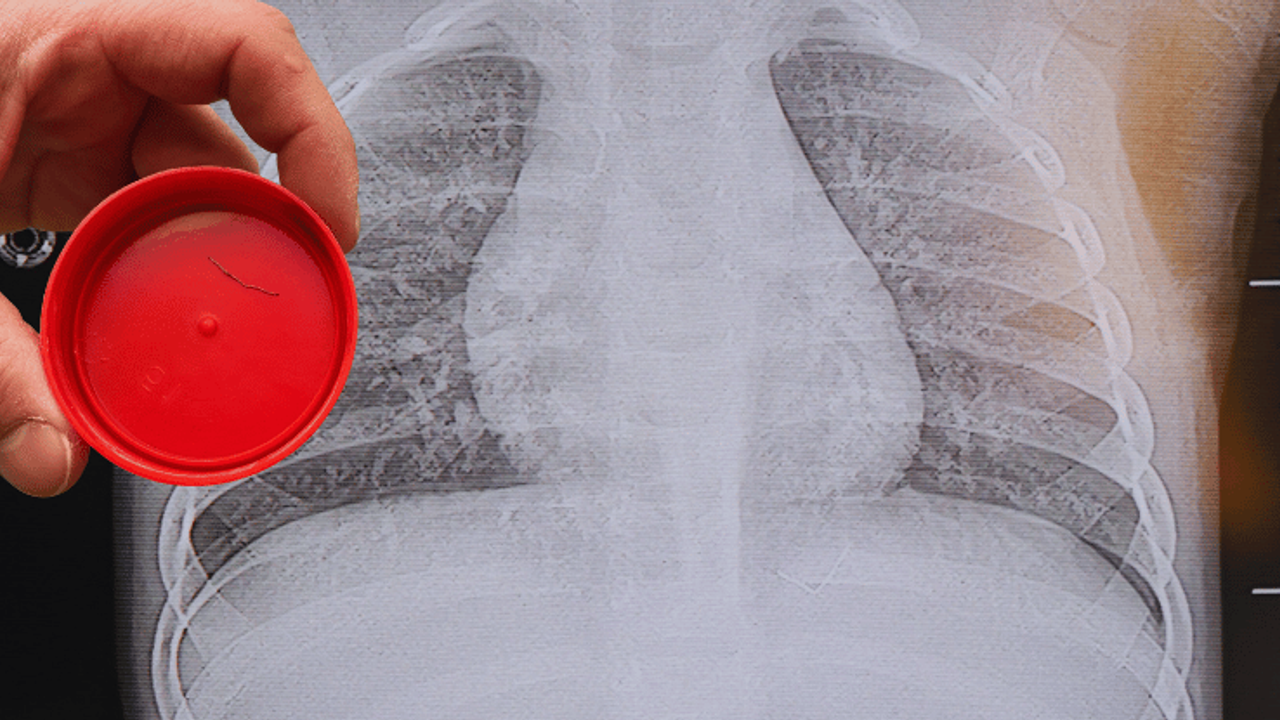

Beyin ve Sinir Cerrahisi Uzmanı Prof. Dr. İdris Altun tarafından yapılan tetkiklerde, yabancı cismin cilt altında, omurilik kanalına yakın bir bölgede olduğu ve akciğer zarına doğru ilerlediği belirlendi. Hasta, genel anesteziye alınmadan, lokal anestezi ve sedasyon eşliğinde ameliyata alındı. Yapılan müdahalede yabancı cisim tamamen çıkarıldı. Çıkarılan cismin, ince zımba teline benzer metal bir tel olduğu ve yaklaşık 2 santimetre uzunluğunda bulunduğu tespit edildi. Hasta, aynı gün taburcu edildi.

Konuya ilişkin açıklama yapan Prof. Dr. İdris Altun, "Sırtında yabancı bir cisim olduğu söylenmiş ancak çıkarılamayacağı ve 8 yaşına kadar beklenmesi gerektiği ifade edilmişti. Bize başvurduğunda yaptığımız tetkiklerde, cilt altında, omurilik kanalına çok yakın ve akciğer zarına doğru ilerleyen bir yabancı cisim tespit ettik. Hastamızı tamamen uyutmadan, lokal anestezi ve sedasyon eşliğinde müdahale ederek lezyonu tamamen çıkardık. Çıkardığımız cismin ince zımba teline benzer, yaklaşık 2 santimetre uzunluğunda metal bir tel olduğunu gördük. Bu yabancı cisim alınmasaydı, bölgede enfeksiyon gelişebilirdi. Enfeksiyon sonucu omurilik kanalında ciddi hasarlar oluşabilir, çocuk büyüdükçe cismin hareket etmesine bağlı olarak omurilikte zedelenmeler meydana gelebilirdi. Ayrıca yana doğru ilerleyerek akciğer zarına ve akciğere batma riski vardı. Bu da enfeksiyona ve ilerleyen süreçte tümörle karışabilecek tablolara neden olabilirdi. Şu an hastamız gayet sağlıklı. Gerekli kontrolleri yaptık ve aynı gün taburcu ettik" dedi.